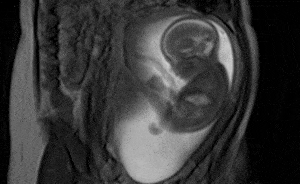

إنّها حتماً من بين اللحظات المميزة التي تتذكرها كلّ أم خلال حملها والتي تستمتع بها، فها هي تشعر بصغيرها يتحرك داخلها، ليقدم على الركل وكأنّه يذكرها: "ماما، أنا هنا!" ولكن، ما السبب الفعلي وراء هذه الركلات التي يقوم بها الجنين؟ الأمر ليس كما تتوقعينه، وسنكشفه لكِ فيما يلي!

من المعروف أن الأم تشعر بـبدء حركة الجنين بوضوح وبالأخص الركل ما بين الأسبوع الـ16 والـ30، علماً بأنّها قد تختبر شعوراً أقل وضوحاً يعرف بالرفرفة أو الـFluttering إبتداءً من الأسبوع الـ13.

وتجدر الإشارة أن قوّة ركلة الجنين تتزايد مع الوقت، لتصل إلى قوّة تعادل ضغط ما يقارب 4 كيلوغرامات ونصف في الأسابيع الأخيرة من الحمل.

الجنين لا يقوم بكل هذه الركلات للفت إنتباهكِ أو بدافع الملل كما يسود الظن، إذ تبيّن أنّ لهذه الحركات الذي تشعرين بها، أو حتّى ترينها على بطنكِ سبب مهم للغاية. فطفلكِ المستقبلي يقوم بنوع من التمرين لتقوية بنيته بهذا الشكل.

فحركات الركل هذه مهمة للغاية لتعزيز عضلاته ومفاصله، كما أنّها ضرورية لتقوية عظامه. ولعل هذه الركلات تعتبر مؤشراً مهماً لسلامة وقوة العظام والمفاصل لاحقاً مع ولادة الطفل ووصوله حتّى إلى سنّ الرشد.